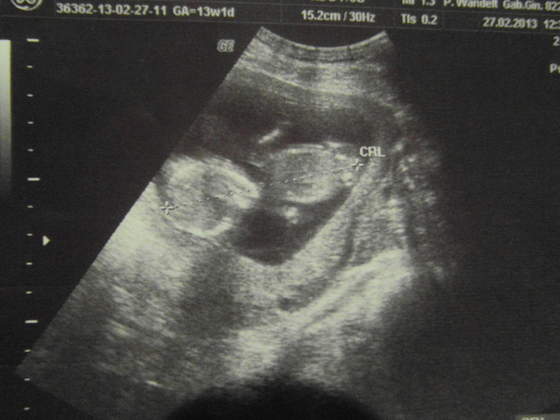

08.06/04.10/09.13

Ja też dzisiaj u ginki byłam. Mam się oszczędzać, taaa. Oczywiście pessar mnie nie ominie, liczyłam się z tym, ale myślałam, że jeszcze nie będzie na ten temat

Kolejna wizyta 14.03.